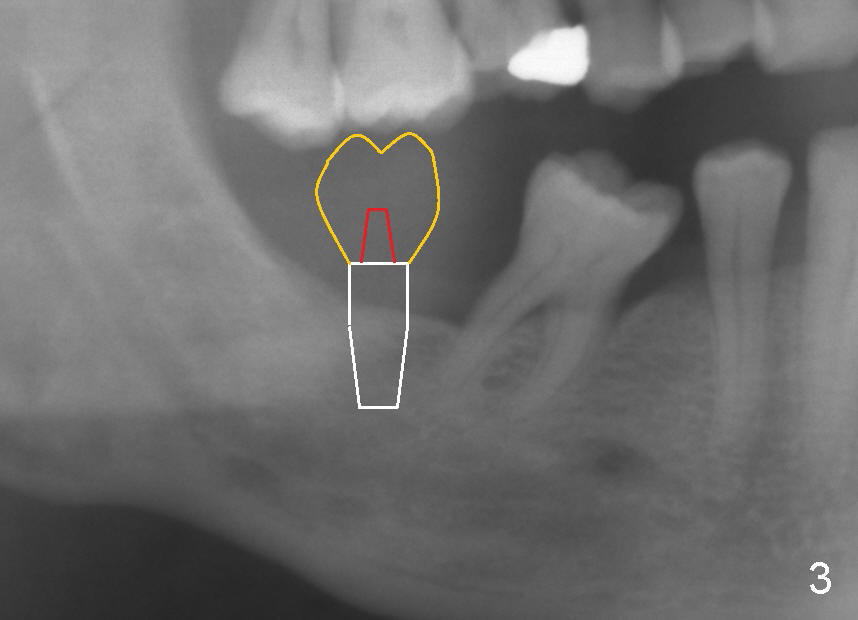

A crown fabricated at the site of #31 should have its normal anatomy (yellow outline in Fig.3; red: abutment; white: implant). The mesiodistal width should not be wide. Do not establish proximal contact with the tooth #30. Make a normal vertical contact with the opposing tooth, #2. Also the buccolingual occlusal table should be approximately 80% of normal dimension.